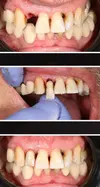

Tooth Loss

Implant Treatment

Zirconium Applications

Porcelain Applications